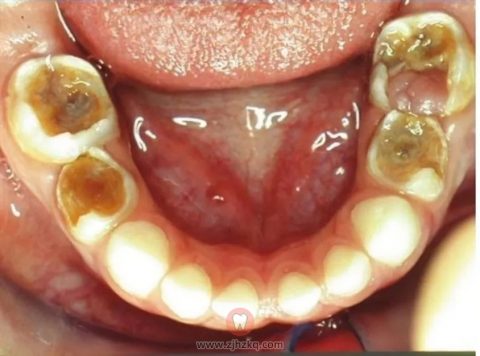

需要做根管治疗的牙齿,是已经出现疼痛或牙神经已经发炎,或甚至已经出现根尖周炎或者是根尖周脓肿了,如果不及时治疗疼痛会一直持续发展,而且有可能会导致恒牙胚受损会导致恒牙的萌出异常,而且这种疼痛会影响儿童咀嚼。

乳牙根管治疗,是通过根管预备和根管消毒,去除感染物质对根尖周组织的不良作用,并用可吸收的充填材料充填根管,防止发生根尖周病,促进根尖周病变愈合的治疗方法,其治疗步骤主要包括术前准备、开髓以及根管填充。